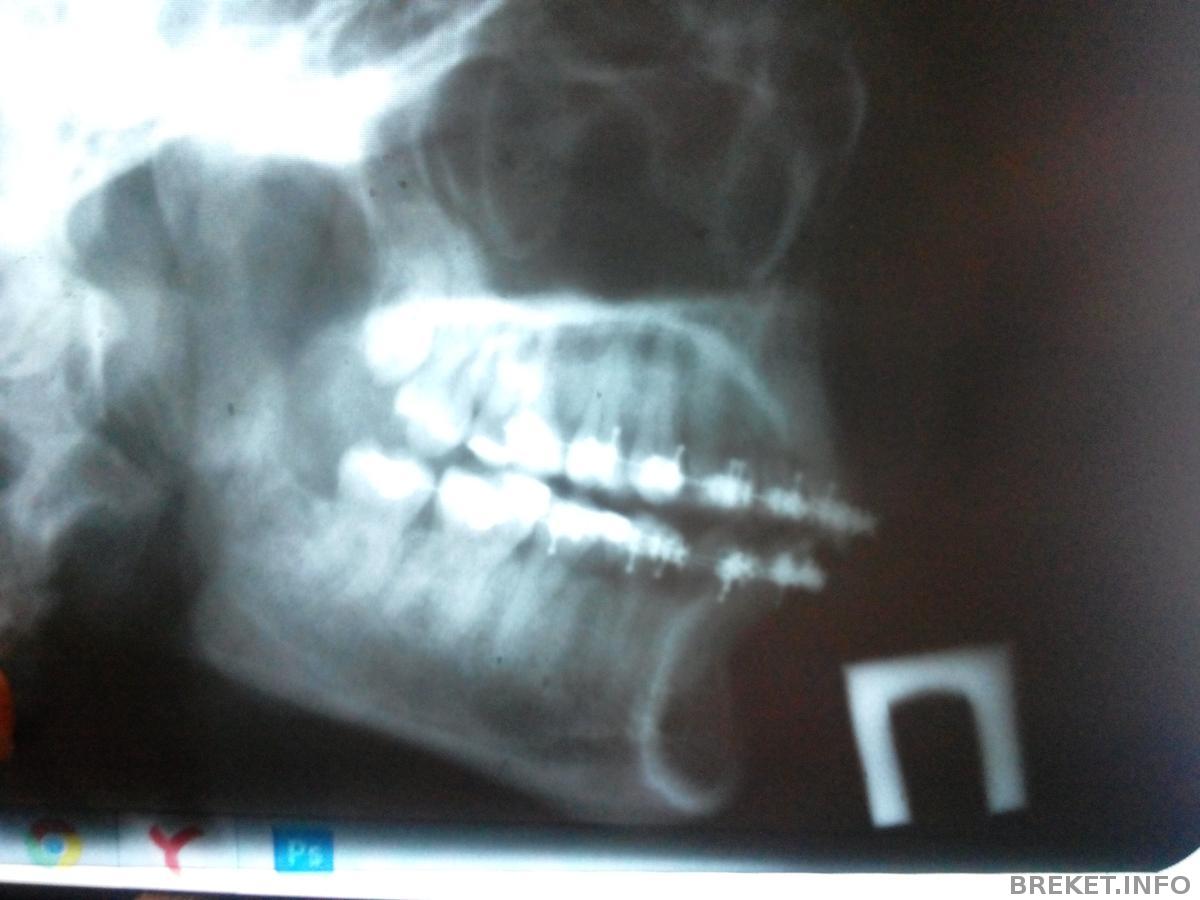

Я сень после снимка....бокового (было подозрение на сотрясение((((( )

зубы расстроили больше всего смыкания нет(((

По поводу смыкания - не бывает все сразу же... ты спроси у орта, что он скажет на счет него. Хотя я по снимку не очень понимаю где там что не так)